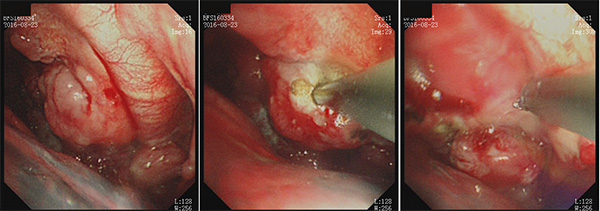

患者大量胸水到底是怎么回事--肿瘤性?肺结核复发?还是其他原因?为了明确诊断,冯起校教授团队决定启用胸腔积液诊疗奇兵--内科胸腔镜手术。术中内科胸腔镜下看的图像令人大吃一惊:胸膜上能看见大量肺癌转移的结节。病人这种情况已失去最佳手术时机,为了减少费用,取活检后,对这些结节进行了高频电切治疗。术后1周,病理结果提示非小细胞肺癌,给予患者1疗程化疗,目前该患者症状好转出院。

以下为该病人内科胸腔镜下手术照片